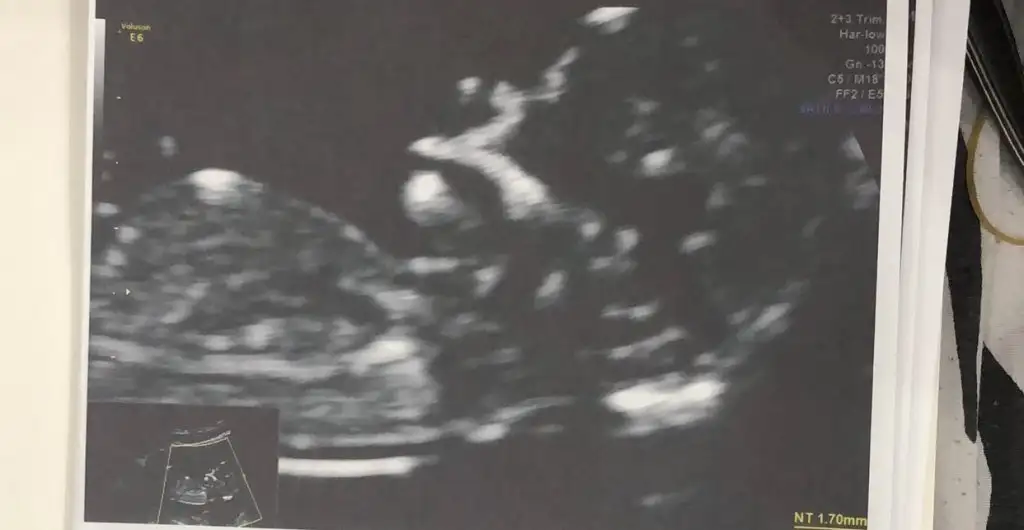

Merhaba , Vajinal ultrason tahmininiz var mı Ikra meyra Ikra meyra

Erkek görünüyor tabiki en iyi 11 12 13 haftalar olmalı

Ikra meyra Ikra meyra canım başka forumda çoğu kullanıcı kız yazmıştı bir sen erkek demiştin. Dün erkek olduğu kesinleşti Allahın takdiri ile. Çok teşekkür ederim